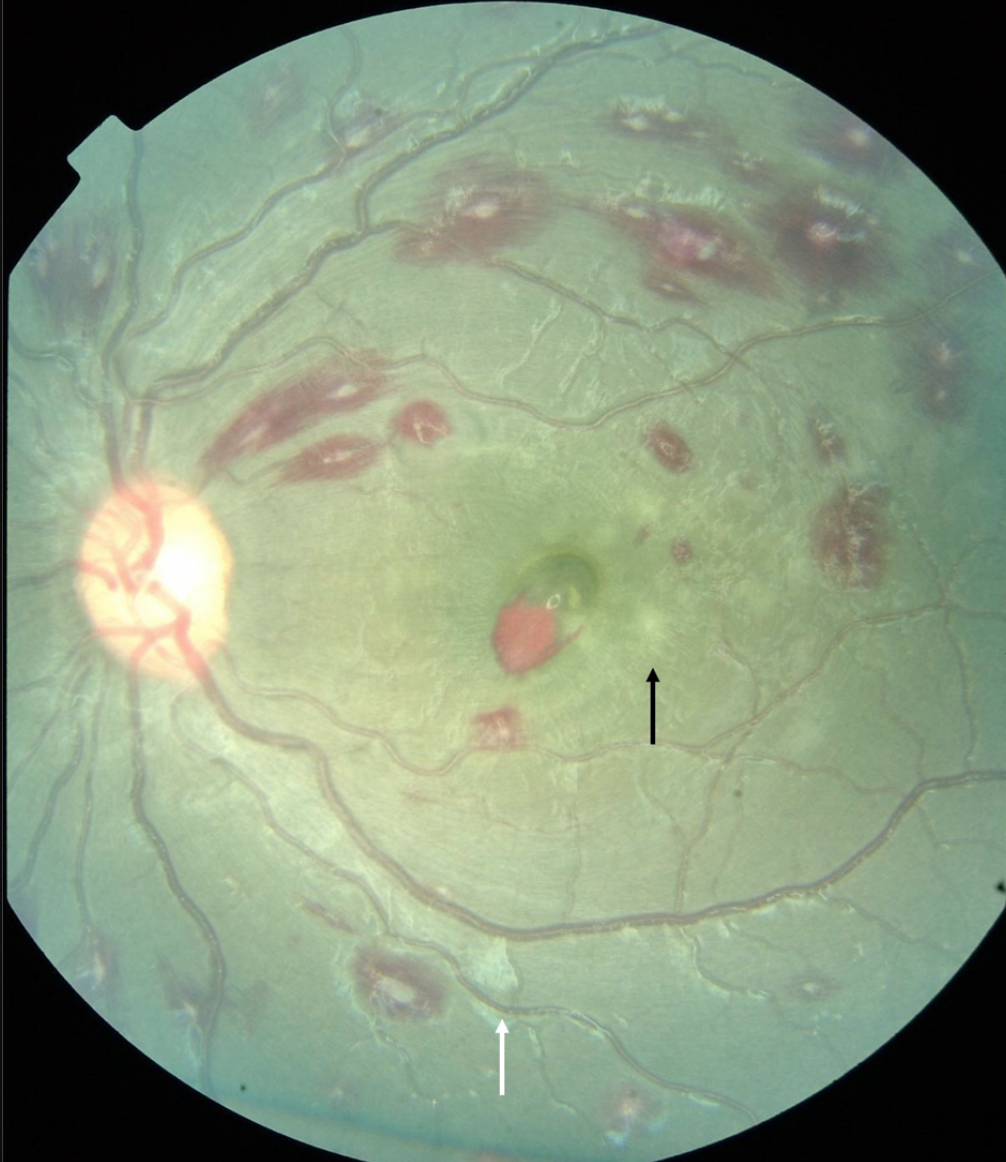

Seen on fundoscopy of cerebral Malaria

White patches on retina (due to focal ischaemia) and haemorrhage

white-centred haemorrhages, a superficial blot haemorrhage at the fovea, mild macular whitening (black arrow) and cotton wool spot (white arrow)